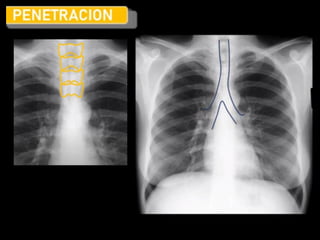

Criterios de ‘calidad’

R.I.P.

• Rotación: Los procesos espinosos se

encuentran en un punto medial entre

las clavículas.

• Inspiración: Al menos 5 a 7 costillas

anteriores o 8 a 9 costillas posteriores

por arriba del diafragma en la línea

medio clavicular. Escápulas fuera del

tórax

• Penetración: Columna debe ser visible

detrás del corazón, vasos en ápices

pulmonares y a través del corazón.

Blanda

Dura

J. Vargas Romero . Aspectos básicos en radiología de tórax EB04-03 Radiología Madrid 2010